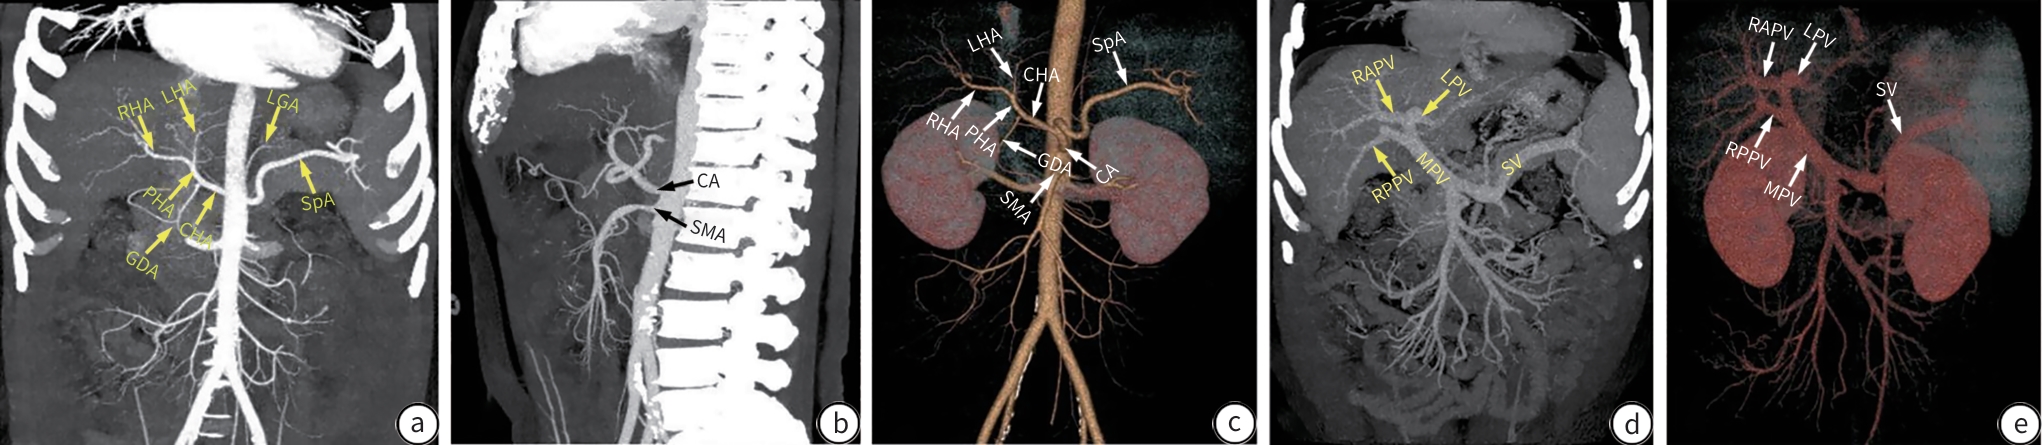

Objective  To investigate the feasibility, safety, and efficacy of surgery-assisted transjugular intrahepatic portosystemic shunt (SA-TIPS) in the treatment of portal hypertension comorbid with complex portal vein thrombosis, including cavernous transformation of the portal vein (CTPV).  Methods  An analysis was performed for the data of 36 patients with portal hypertension and complex portal vein thrombosis who underwent SA-TIPS in Beijing Shijitan Hospital, Capital Medical University, from November 2023 to January 2025, including general status, technical data of the surgical process (surgical success rate, puncture times, time of operation, the number of stents used, and the length of shunt), perioperative complications, and surgical recovery. The change in portal pressure gradient (PPG) after shunt was compared, and the rate of reaching the standard for PPG reduction was calculated, as well as stent patency rate within 1 week after surgery. The paired samples t-test was used for comparison of continuous data between two groups.  Results  Among the 36 patients, 34 (94.4%) underwent SA-TIPS successfully. The incidence rate of perioperative complications was 16.7% (6/36), including 3 cases of thoraco-abdominal hemorrhage, 2 cases of intraoperative arrhythmia, and 1 case of incision infection. There was a significant reduction in PPG after SA-TIPS (t=19.85, P<0.01), and the patients achieving a ≥50% reduction in PPG accounted for 76.5% (26/34). Imaging reexamination within 1 week showed a shunt patency rate of 100%.  Conclusion  SA-TIPS has a high technical success rate, a favorable safety profile, and good efficacy in the treatment of portal hypertension comorbid with complex portal vein thrombosis (including CTPV), and therefore, it holds promise for clinical application.